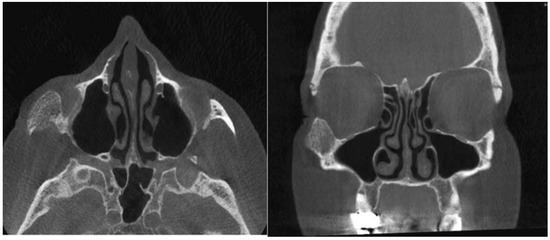

- Moore, S.L.; Chun, J.K.; Mitre, S.A.; Som, P.M. Intraosseous hemangioma of the zygoma: CT and MR findings. AJNR Am J Neuroradiol 2001, 22, 1383–1385. [Google Scholar] [PubMed]

- Razek, A.A. Imaging appearance of bone tumors of the maxillofacial region. World J Radiol 2011, 3, 125–134. [Google Scholar] [PubMed]

- Gonçalves, F.G.; Rojas, J.P.; Hanagandi, P.B.; et al. Case report: Periorbital intraosseous hemangiomas. Indian J Radiol Imaging 2011, 21, 287–290. [Google Scholar]